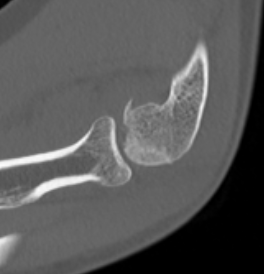

Coronal shear fracture of the distal humerus

Capitellum +/- trochlea

Dubberly Classification

Type I Type Ii Type III

Capitellar fracture

Capitellum + trochlea fracture

In one piece

Double arc sign seen on xray

Capitellum + trochlea fractures

In two separate pieces

Double arc sign on xray